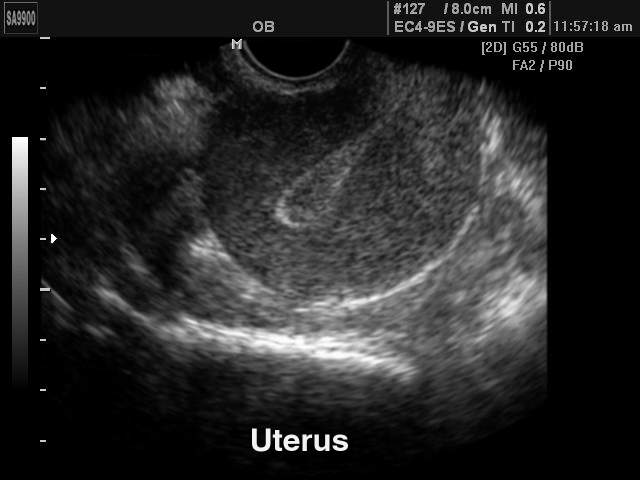

Матка

Гинеколог, начиная осмотр органа, оценивает расположение в брюшной полости. Матка может быть немного отклонена к прямой кишке или мочевому пузырю. На нормативные значения размеров матки оказывает влияние количество лет пациентки, роды в анамнезе, пребывание в менопаузе. Оценивая допустимое отклонение размеров матки от нормы, доктор принимает во внимание на день менструального цикла УЗИ сканирования.

Положение органа

Матка располагается между мочевым пузырем и прямой кишкой. Она немного смещается при сильном наполнении мочевого или кишечника, а также во время беременности. В норме тело матки обращено кпереди, что называется антеверсией.

При повороте тела матки к боковой стенке таза говорят о латероверсии, а смещение кзади свидетельствует о ретроверсии.

Контуры органа

При отсутствии патологий контуры органа четкие и ровные. Нечеткие контуры свидетельствуют о наличии миомы, опухоли или ракового заболевания. Если размыты внешние очертания, велика вероятность параметрита – воспаления тканей, которые окружают матку.